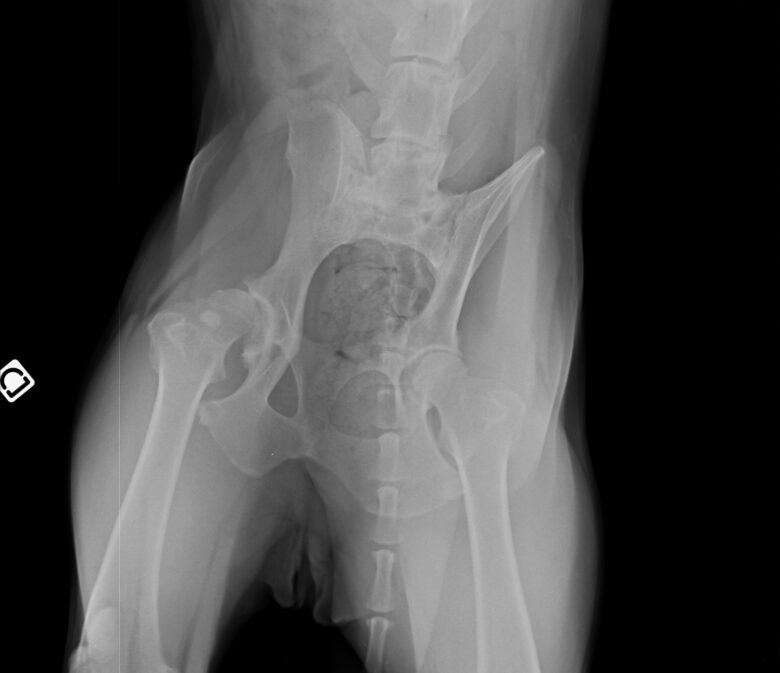

Nous avons choisi de faire une radio et c’est là que nous avons découvert l’impensable : Helly est atteinte d’une dysplasie très importante ainsi que d’arthrose et de becs de perroquet – les vertèbres se soudent entre elles et réduisent drastiquement la mobilité – à de multiples endroits.

Après un premier rendez-vous avec le spécialiste Dr Wiliam RANDLE à la Yourte Vétérinaire pour confirmer qu’Helly était éligible à cette pratique au regard de ses pathologies et des images radios, nous avons convenu d’une opération un mois plus tard début avril 2025.

L’intervention dure 30 à 40 minutes avec une sédation légère – ils n’intubent pas le chien a priori sauf exception – et le vétérinaire va venir déposer avec une grosse aiguille les implants d’or sur les zones prédéfinies. Helly a reçu 32 implants au total sur les hanches, la colonne et les poignets. A la Yourte, ils ne rasent que les zones nécessaires contrairement à d’autres cliniques qui rasent intégralement les hanches du chien par exemple.